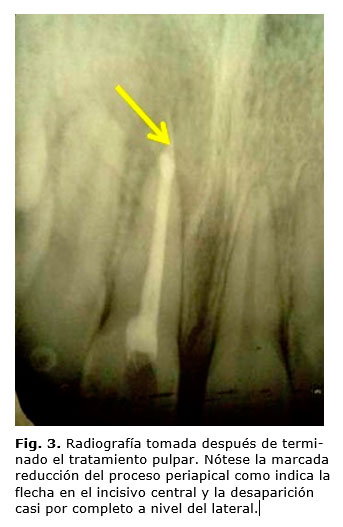

A la paciente le fue realizada una necropulpectomía en incisivo central conjuntamente con un raspado y alisado radicular en el lateral. Luego de 10 días de realizado el tratamiento periodontal el aumento de volumen granulomatoso a nivel del incisivo central había desaparecido casi por completo y se observó la reducción del tamaño del proceso a nivel del incisivo lateral (fig. 3).

El proceso de recuperación fue evaluado mediante exámenes radiográficos periódicos durante un período de 6 meses, al cabo del cual se apreció la recuperación del ligamento periodontal y claros signos de regeneración ósea. Clínicamente se apreció surco gingival de 2 mm, sin sangramiento u otro signo patológico.